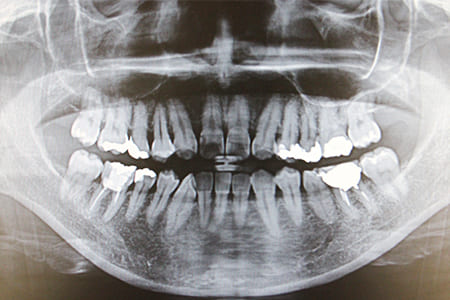

レントゲン検査

初期のむし歯や歯と歯の間の眼では見えないむし歯をレントゲンで確認します。

その他歯ぐき内部の骨の状態や歯根のう胞、神経の炎症などを確認します。

インプラントにおいては、周囲の骨の状態や接合装置・補綴物の適合状態などを確認します。